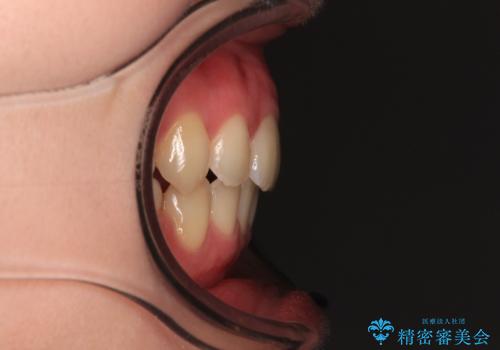

【モニター】横顔のシルエットをスッキリと ワイヤー装置による抜歯矯正治療

- 前歯のデコボコと突出感を気にして来院された患者様です。

上下左右第一小臼歯4本を抜歯して、積極的に口元を引っ込めるよう、ワイヤー装置にて矯正治療を行うこととしました。